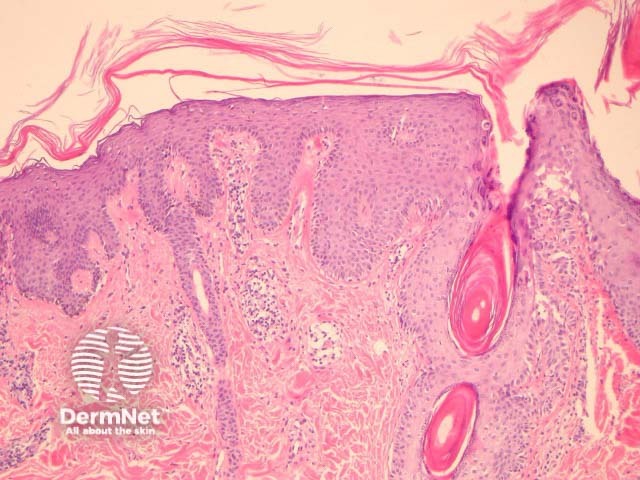

Pityriasis rubra pilaris or PRP presents clinically as a papulosquamous eruption with follicular plugging and perifollicular erythema. The various clinical forms share the same histopathologic features.

In PRP, the epidermis shows regular acanthosis and psoriasiform hyperplasia (figures 1-3). The horn is thickened with parakeratotic foci between orthokeratosis both vertically and horizontally (not seen clearly in the presented images). The hyperkeratosis tracks down the openings of follicular structures forming follicular plugs (figures 1-3). The dermis may contain a mixed sparse infiltrate which may be lichenoid. Rarely, foci of acantholysis may be seen (figure 3) and some authors have made associations with Darier disease.

Figure 1